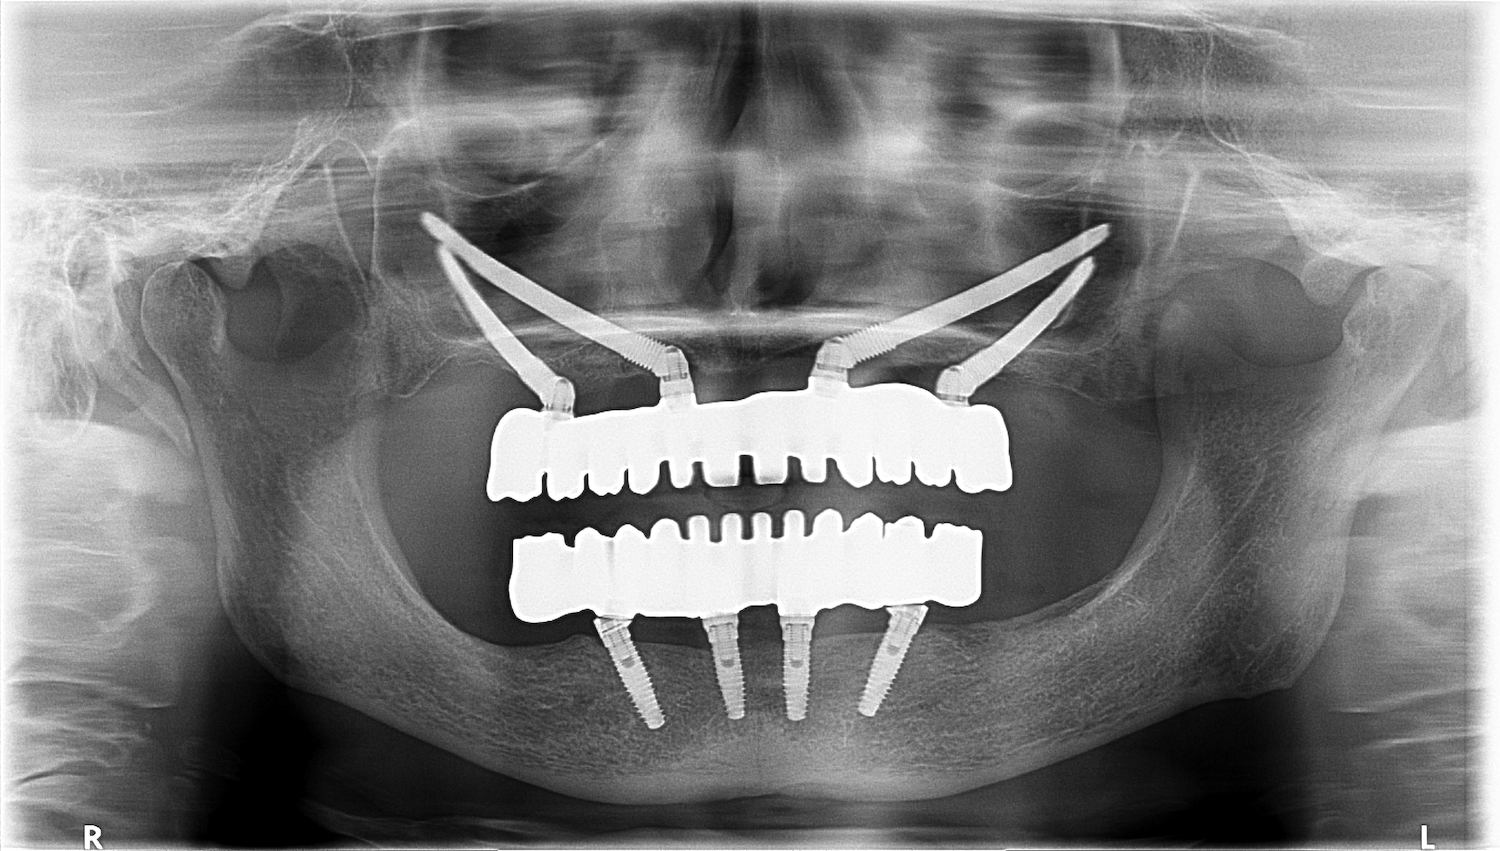

Normalmente, se colocan dos implantes cigomáticos en la parte posterior del maxilar, que se combinan con dos o más implantes convencionales en la parte anterior. Esto permite ofrecer una prótesis fija y una distribución óptima de la carga masticatoria.

En Clínica Curull, contamos con un equipo experto en implantología avanzada, liderado por especialistas en técnicas mínimamente invasivas y cirugía guiada. Gracias al uso de escáneres 3D, planificación digital y simulaciones virtuales, garantizamos la precisión absoluta en la colocación de implantes cigomáticos.

Casos clínicos de éxito

Hemos rehabilitado con éxito a decenas de pacientes que, tras años con prótesis removibles o sin soluciones viables, han logrado volver a sonreír y comer con confianza gracias a esta técnica revolucionaria. Nuestros resultados clínicos están avalados por fotografías, testimonios y seguimientos a largo plazo.